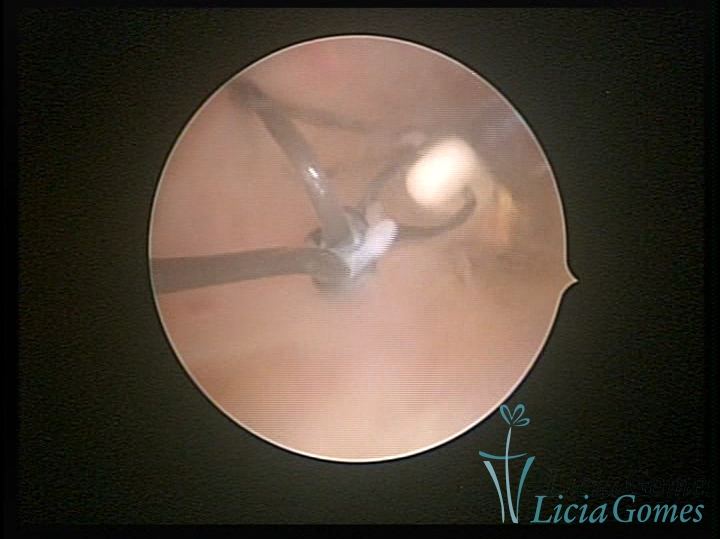

Cavidade com o Mirena®, sendo retirado sob visão direta

×